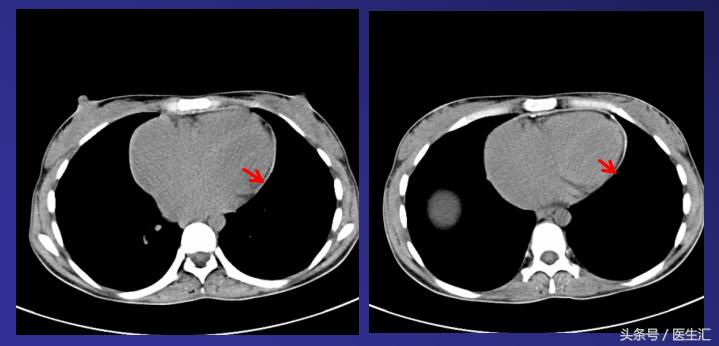

2011-10-24 腹部CT:肝硬化、脾大(9个肋单元);三支肝静脉增宽,未见充盈缺损;下腔静脉未见明显异常;肝内胆管轻度扩张

2011-11-18胸部CT:双房增大,心包均匀增厚,可见明显钙化灶,考虑缩窄性心包炎。